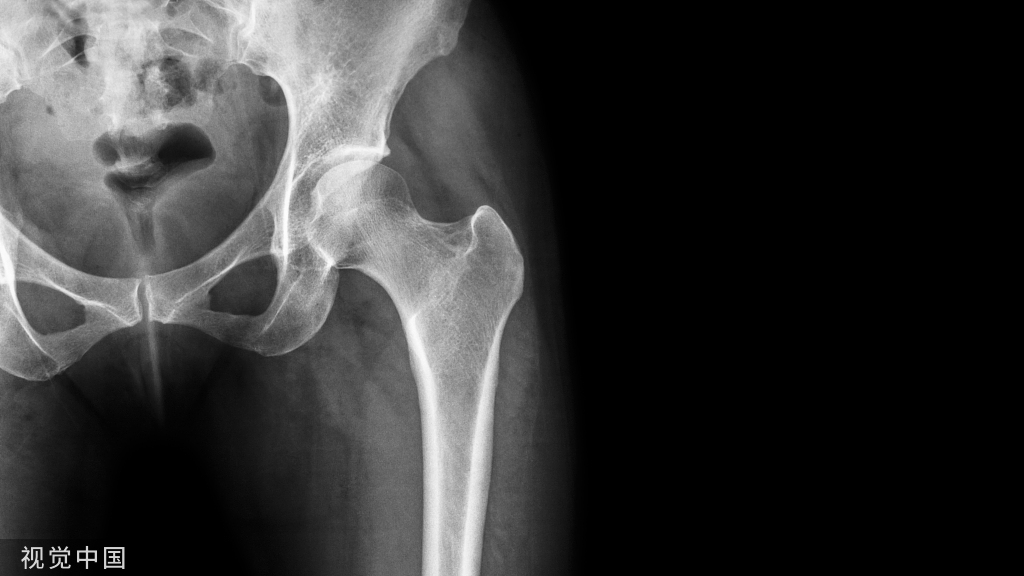

髋关节脱位是骨科常见急诊,遇到脱位一定要复位,但是复位可不是那么容易的呀,俗话说胳膊再粗掰不过大腿,今天介绍一种复位方法。

最常见的仪表盘类损伤常伴随后脱位,需要行X线进行脱位的确诊